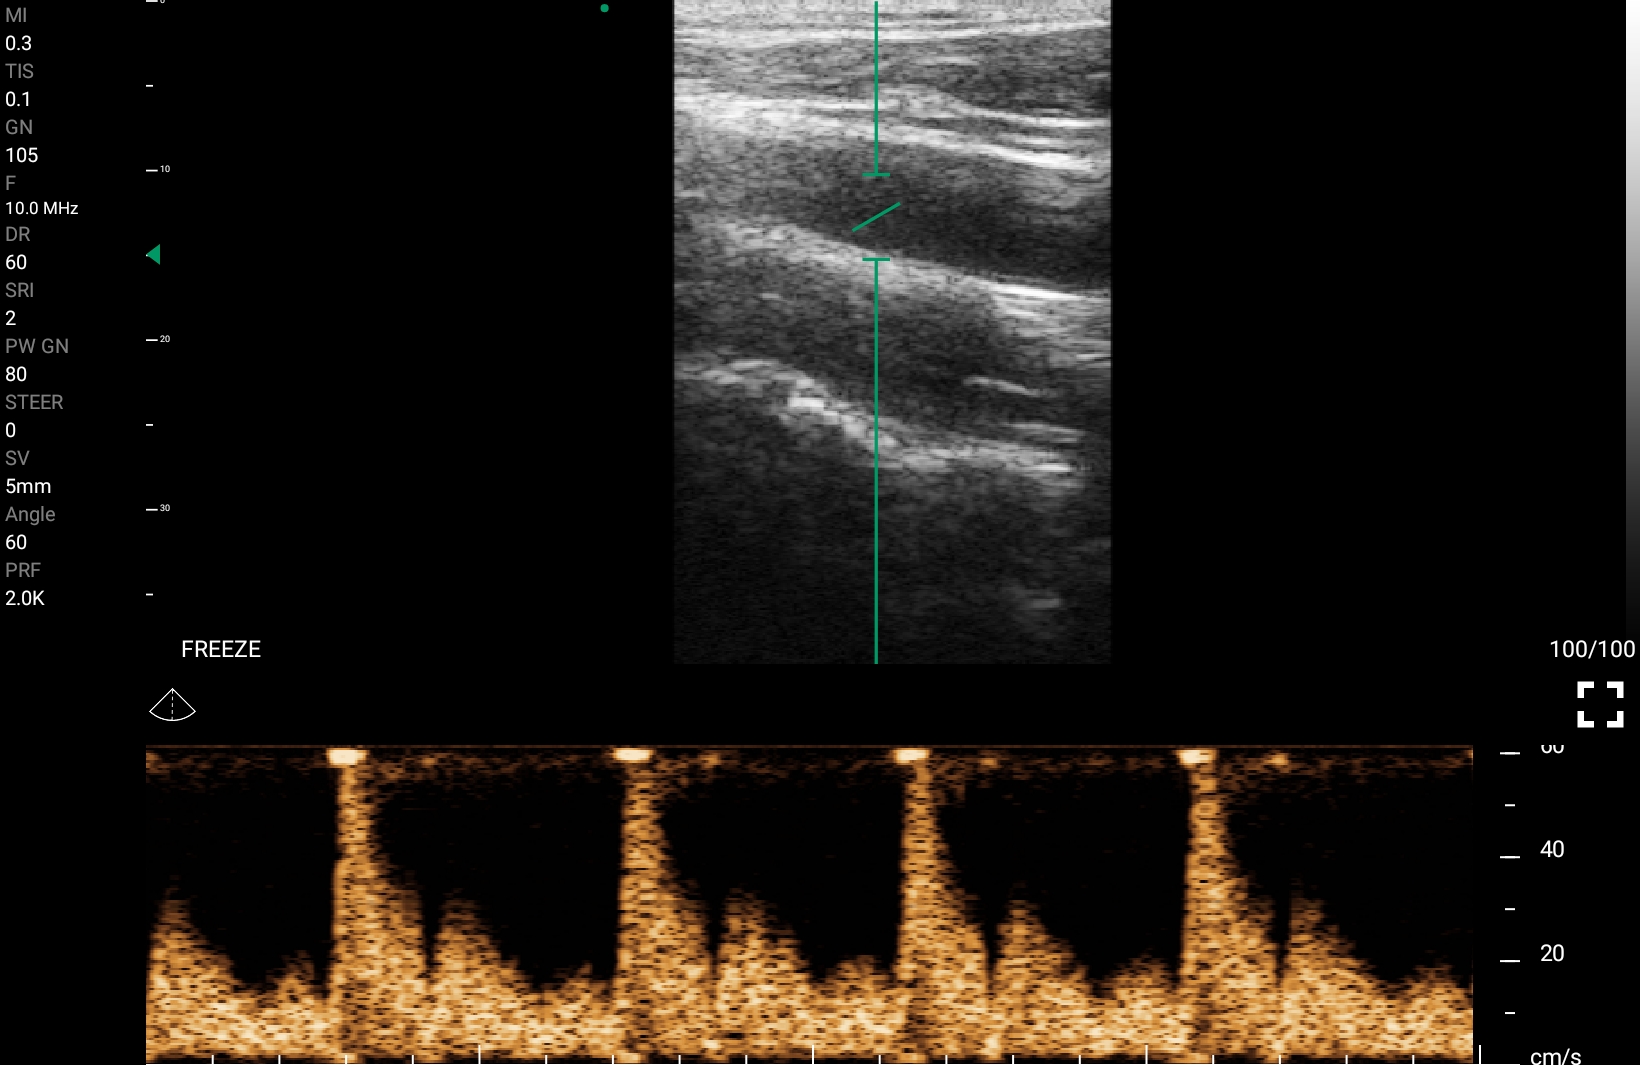

Παραδείγματα

Ολες οι παραπάνω απεικονιστικές εξετάσεις έχουν ληφθεί από φορητή συσκευή όπως: Apple Iphone, Tablet, Samsung Mobile Phones και διάφορες άλλες φορητές συσκευές.

Παραδείγματα Video